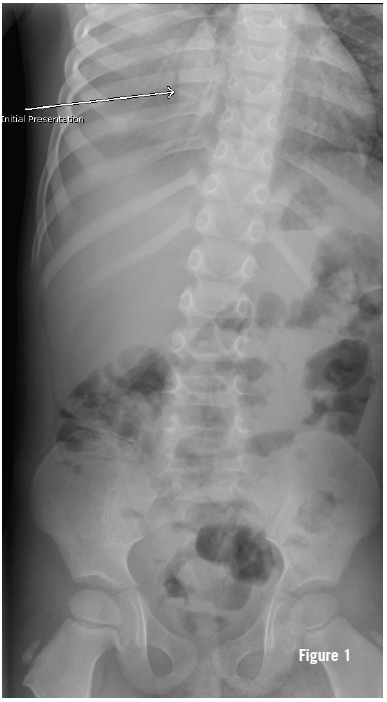

The patient was seen 23 days after the initial ED visit by his primary care physician, who noted minimal retractions, tachypnea (respiratory rate of 48 breaths per minute), and an oxygen saturation of 95% on room air. Results of in-office chest radiography (Figure 1) led to the patient being admitted immediately to a nearby emergency department.

The chest radiograph (Figures 1-3) showed opacification of the right hemithorax, with aeration of the right upper and anterior right lower lung, and a slight mediastinal shift to the left. At this time, the patient was directly admitted.